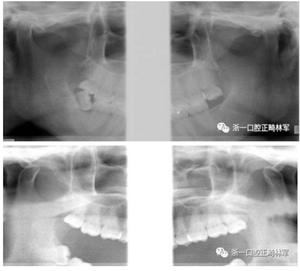

初診張閉口關(guān)節(jié)片:張閉口位關(guān)節(jié)間隙正常。雙側(cè)髁突外形正常,骨皮質(zhì)連續(xù),未見(jiàn)明顯吸收變形。

4.png